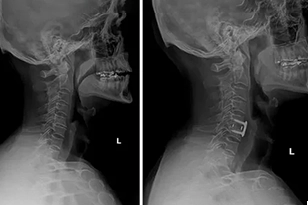

Anterior Cervical Discectomy & Fusion (ACDF)

We remove the damaged disc through a small front-neck incision and fuse the bones. ACDF surgery helps relieve nerve compression and stabilizes the cervical segment to stop pain and weakness.

We do not fuse it, we extract the diseased and replace this with an artificial disc. Replacement of the disc in cervical surgery maintains natural movement in the neck and limits pressure on the neighboring vertebrae.